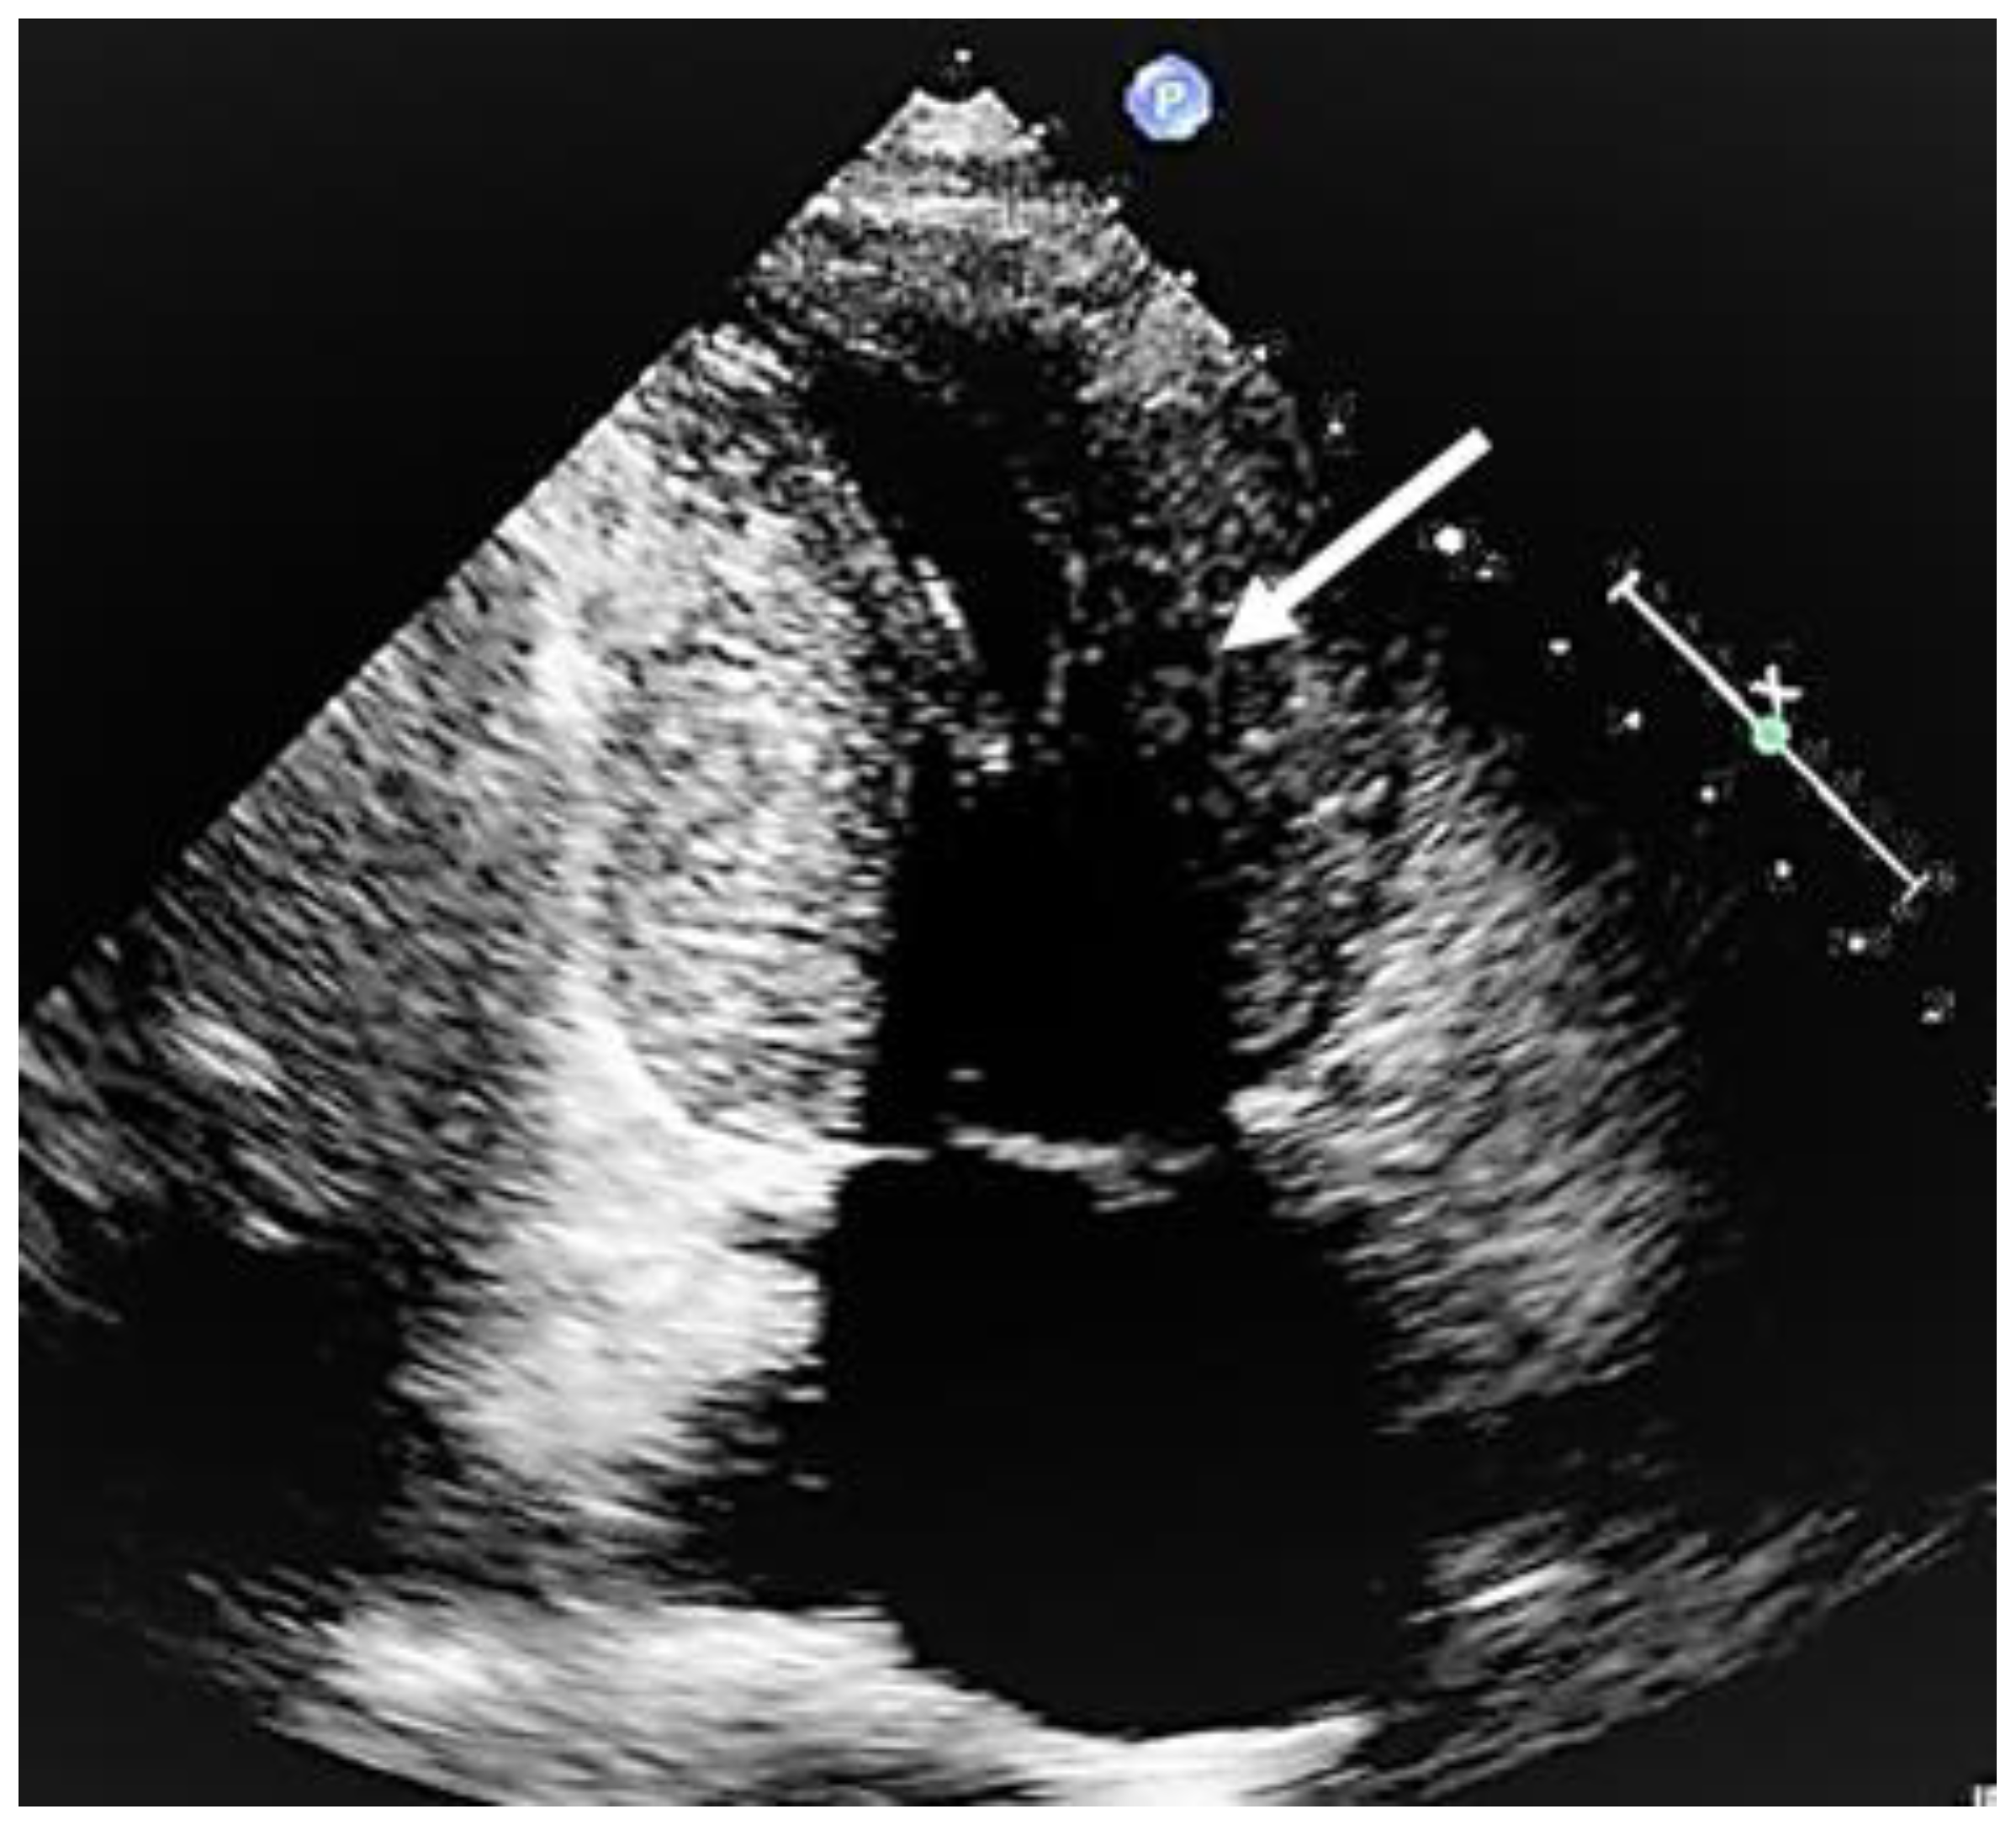

Figure 5. Mid-cavity obstruction; typical hourglass appearance of left ventricle (arrow).

When evaluating the presence and severity of obstruction in HCM, a systematic assessment of all the components of the mitral valve apparatus via 2D echocardiography is required. This technique allows a visualization of the presence and distribution of LV hypertrophy, the presence of SAM, elongation of mitral valve leaflets, displacement of papillary muscles, laxity of tendon cords and LVOT diameter reduction (Figure 2). In addition, 2D echocardiography allows a diagnosis of MCO via the observation of a typical hourglass appearance of the LV due to systolic septal contact with the anterolateral wall, which induces sphincter-like cavity obliteration, creating two distinct (basal and apical) LV chambers (Figure 5). In addition, 2D echocardiography allows a visualization of the presence of an apical aneurysm and any thrombotic formation. In this setting, contrast echo may also be helpful for the correct diagnosis.